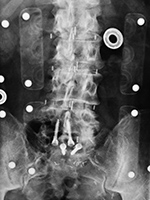

| Vertebral compression fracture treated by expandable corpectomy device |

Interbody vertebral cages |

Bone stimulator |

| There are also bilateral pedicle screws and connecting rods above and below the level of the fracture. |

The cages are at L1-2 with bilateral pedicle screws and rods going from L1 to L3 for degenerative lumbar spine disease. |

The battery pack overlies the right 12th rib. Wires are going to the bilateral bony fusion masses. There is a laminectomy from L2 to L5 with bilateral pedicle screws and a pedicle plate on the right and a connecting rod on the left. Brantigan vertebral cages are at the L5-S1 disk space. |